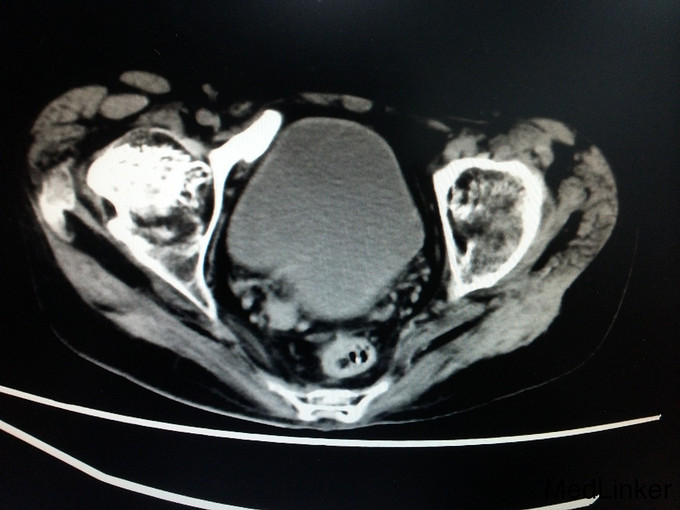

诊断:强直性脊柱炎(累及双侧髋关节) 患者腰骶部活动受限,影像学提示患者双侧骶髂关节间隙消失,且患者HLA—B27异常,强直性脊柱炎诊断明确。患者双髋关节间隙消失,活动度丧失,累及髋关节诊断明确。具有明确手术指症。患者既往关节鳞屑病,现控制稳定,经皮肤科会诊后排出手术禁忌症。由于经济稳定,患者及家属决定分次手术,本次手术暂行右侧人工全髋关节置换术。

讨论: 经验:强直性脊柱炎累及双髋的患者行全髋关节置换术时,显露及找到髋臼是手术的重点和难点。 1.显露。由于髋关节强直,失去活动度,助手在不能旋转大腿,造成显露困难。我们的做法是先充分显露小粗隆,沿小粗隆上方约2cm处截骨(一般常规于小粗隆上方0.5-1cm处截骨),充分离断头颈部,此时助手可通过内旋患肢,充分显露。下一步再按常规行小粗隆上截骨。 2.清除瘢痕组织。此类患者由于长期髋部强直,活动受限,周围往往会形成瘢痕挛缩,多以内收肌紧张常见。故显露的过程需彻底清除周围瘢痕组织。术中安装假体后测试关节各方西活动,若内收肌紧张,需行内收肌松解。 3.找髋臼。由于强直性脊柱炎累及髋关节需行关节置换的患者,往往头与髋臼已经发生融合,术中很难判断髋臼。若贸然凿除所谓的股骨头,很可能会破坏髋臼壁。故找髋臼时性循序渐进,逐渐凿骨找到髋臼。CT片显示头与髋臼底之间仍有间隙存在,故可推断圆韧带仍存在,这也是这类患者的特点。故逐渐凿除股骨头时,到达圆韧带的层面时就找到了髋臼底。此时可开始磨钻磨锉髋臼。从小号开始依次增大号数。 4.骨质。强直性脊柱炎的患者因长期服用激素类药物,骨量丢失较正常人较多,故髋臼骨质疏松明显,所以磨搓髋臼时需反转,防止骨量过度丢失,磨穿髋臼。 不足:1.术中由于患者左髋强直,摆放手术体位受限,不能维持身体中立位,身体后仰,术中安放臼杯时未能把握合适的前倾角度。 2.假体的选择。由于术前未认真评估股骨髓腔的形态,导致术中按常规选择股骨假体柄后,出现假体柄打入困难。该患者股骨髓腔形态呈烟囱型,最好选择直柄,打入后可更贴合,方便骨长入。